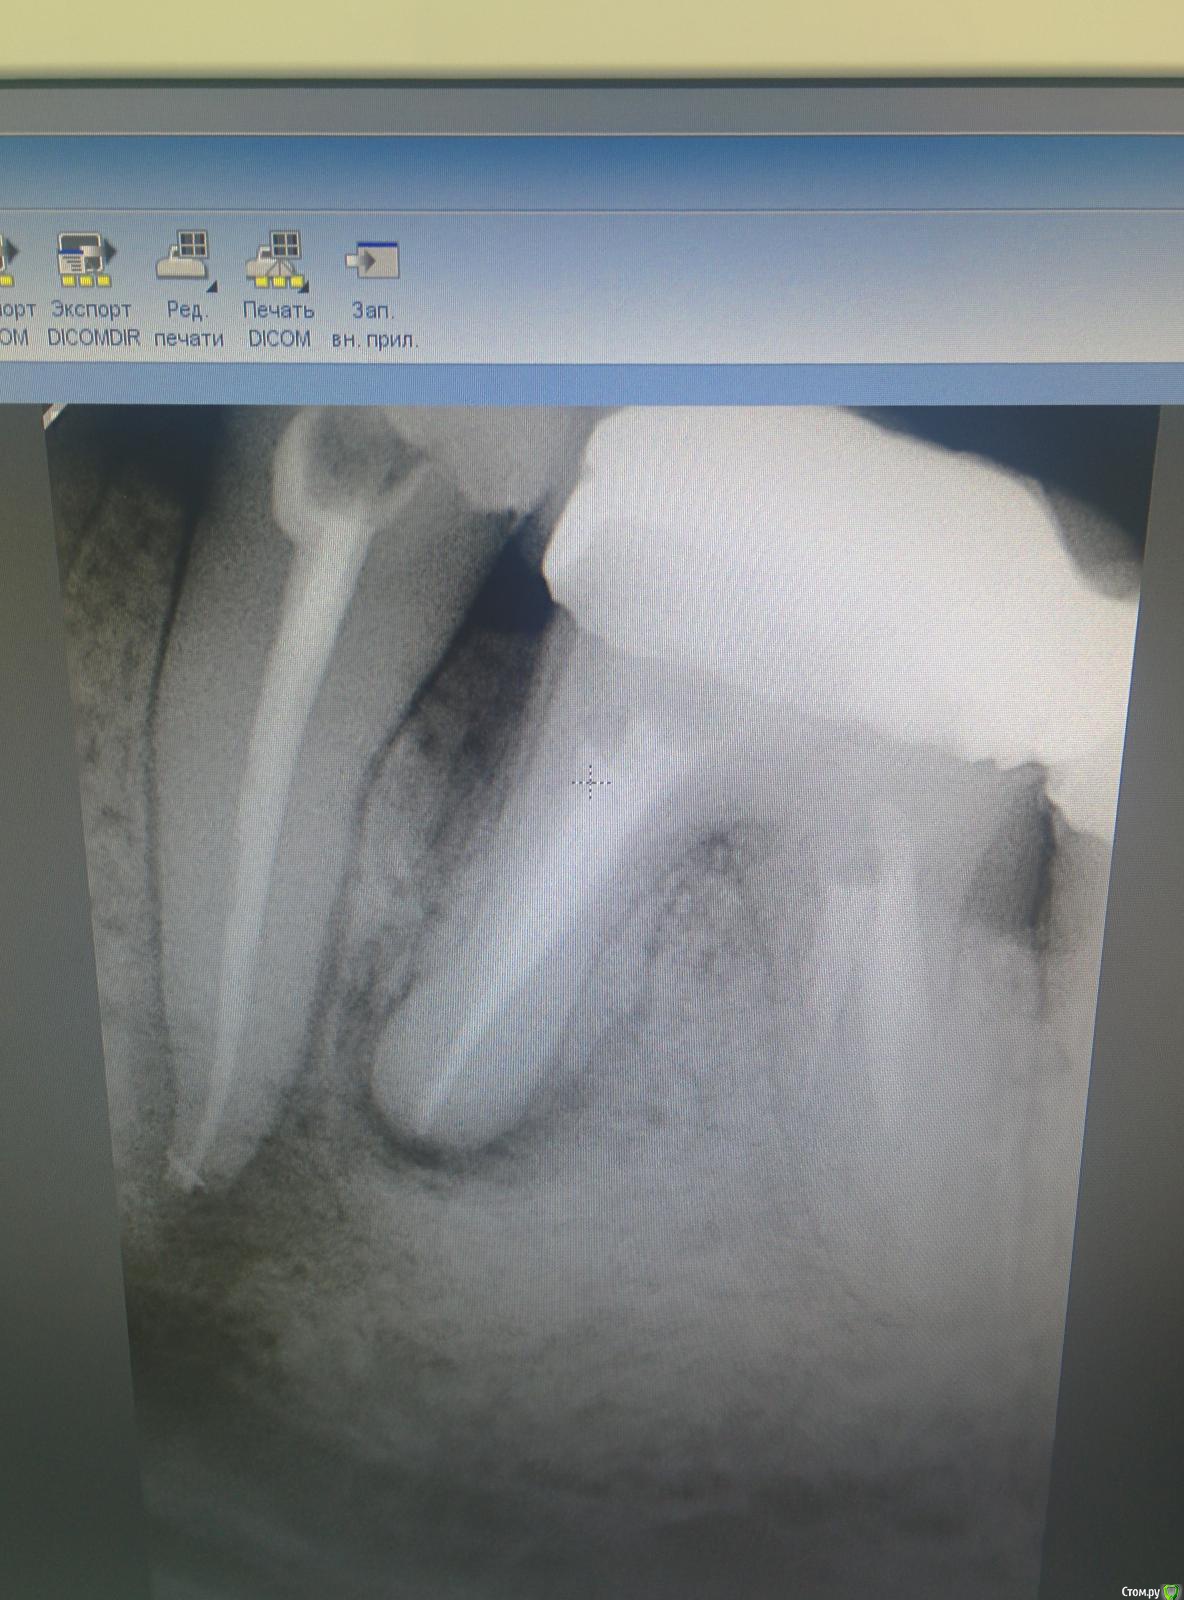

mermaid Опубликовано 18 февраля, 2015 Поделиться Опубликовано 18 февраля, 2015 Добрый вечер!ситуация следующая пол года назад в клинику пришла пациента с отеком на нижней челюсти слева.делаем снимоксразу думала 36,но перкуссия +только в 35,открыли,промыли(эдта+хлорка) ,Са,через 2 недели закрыла постоянно акросил+шрифты Через пол года рецидив,снова отек(36 лечить пациентка всячески отказывалась,уж очень не хотела снимать мостик)и снова перкуссия исключительно на 35 положительна,распломбировала,нашла подобие 2ого канала,долго мыла эдта,тёплой хлоркой,са.через 2 недели в день пломбировки снова отек....и опять мыла в коффере около часа,са.ещё через 2 недели пломбировка Поставили пломбочку...а через неделю звонок...снова отекли!!разобрали все-таки 36(резорцин более 20 лет,10 лет назад попытка перелечивания,костный карман..перфо в дистальном..хирург чешет лапки)Пациентка устала и готова к удалению(((где косяк???p.s.зондирование по по маргинальному краю в поисках трещины проводила,но провалов нетP.s.ещё смущает наличие плотного костного выбухания в области 35 Ссылка на комментарий

SDC Опубликовано 18 февраля, 2015 Поделиться Опубликовано 18 февраля, 2015 Про 36все понятно,перфо было старое,закрытое гуттой.Интересует лечение 35,что ещё предложите попробоватьНаблюдение. Если пообсуждать, то нужно пару прицельных снимков в боковых проекциях Ссылка на комментарий

SDC Опубликовано 18 февраля, 2015 Поделиться Опубликовано 18 февраля, 2015 Ок,а с обострениями как быть??распломбировка и Са???Из Вашего рассказа я понял, что причиной последнего обострения был признан 6-й зуб и он еще не удален. Предположим, что 6 удален, но вновь возникло обострение в этом регионе и это произошло до того, как Вы пригласили пациента на рг-контроль.В таком случае, если Вы уверены в проведенном эндо, планируется апико с ретроградной пломбировкой.Если не уверены, то распломбировка и гидроокись и опять по новой, рг-мониторинг и решение об апико. Ссылка на комментарий